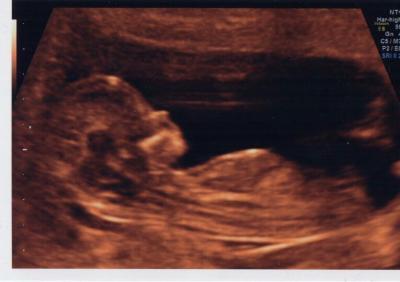

Also. Wir hatten heute Feindiagnostik mit NFM. Und besser hätte die Untersuchung nicht laufen können. Nackenfalte unauffällig und auch sonst alles genauso wie es sein soll. Die Ärztin meinte, wir hätten voll das Streberbaby. :D Und zu meiner großen Überraschung und Freude sieht es zur Zeit mit einer 70% igen Wahrscheinlichkeit so aus, als würde es ein Mädchen. Mein Mann ist superstolz und ich bin auch hin und weg von unserm kleinen Würmchen. Herztöne haben wir auch zum ersten Mal gehört heute, da ist mir dann schon ein Tränchen gekullert. Und ein süßes Foto gab's auch dazu.

Bild zu Heutige NFM - Forum für August - Mamis